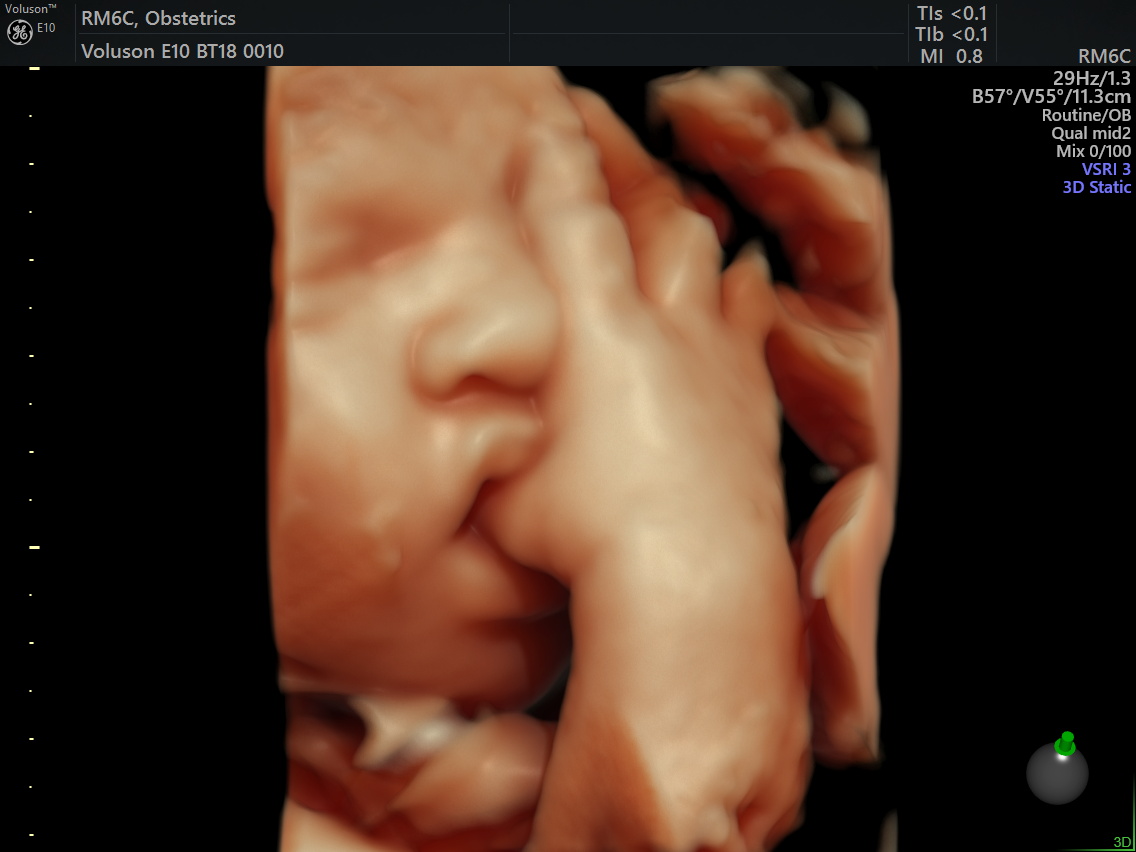

做四维彩超去看胎宝0岁写真,却遭遇胎宝“闭门发布时间:2023年12月1日

吃饭、睡觉还是在玩脐带?

你也好奇胎宝在肚子里玩些什么?

想要做四维彩超更清楚地看见腹中的宝宝

并为Ta留下珍贵的0岁写真相册

有位孕妈说做四维,小宝宝一点不“配合”,医生说脸没转过来看不到面部特征,所以只能出去溜达会儿再来照,溜达了半个小时再回来照,小家伙还是挡住脸。一上午折腾了三次,宝宝都是用手捂住脸。孕妈被折腾坏了,真是欲哭无泪啊!

其实四维彩超除了可以看到胎儿的动态写真,更重要的是能排畸、能监测到胎儿发育、能了解羊水状况。因此,四维彩超虽然比较折腾,建议孕妈还是多点耐心,在四维彩超适宜时间内做完检查。